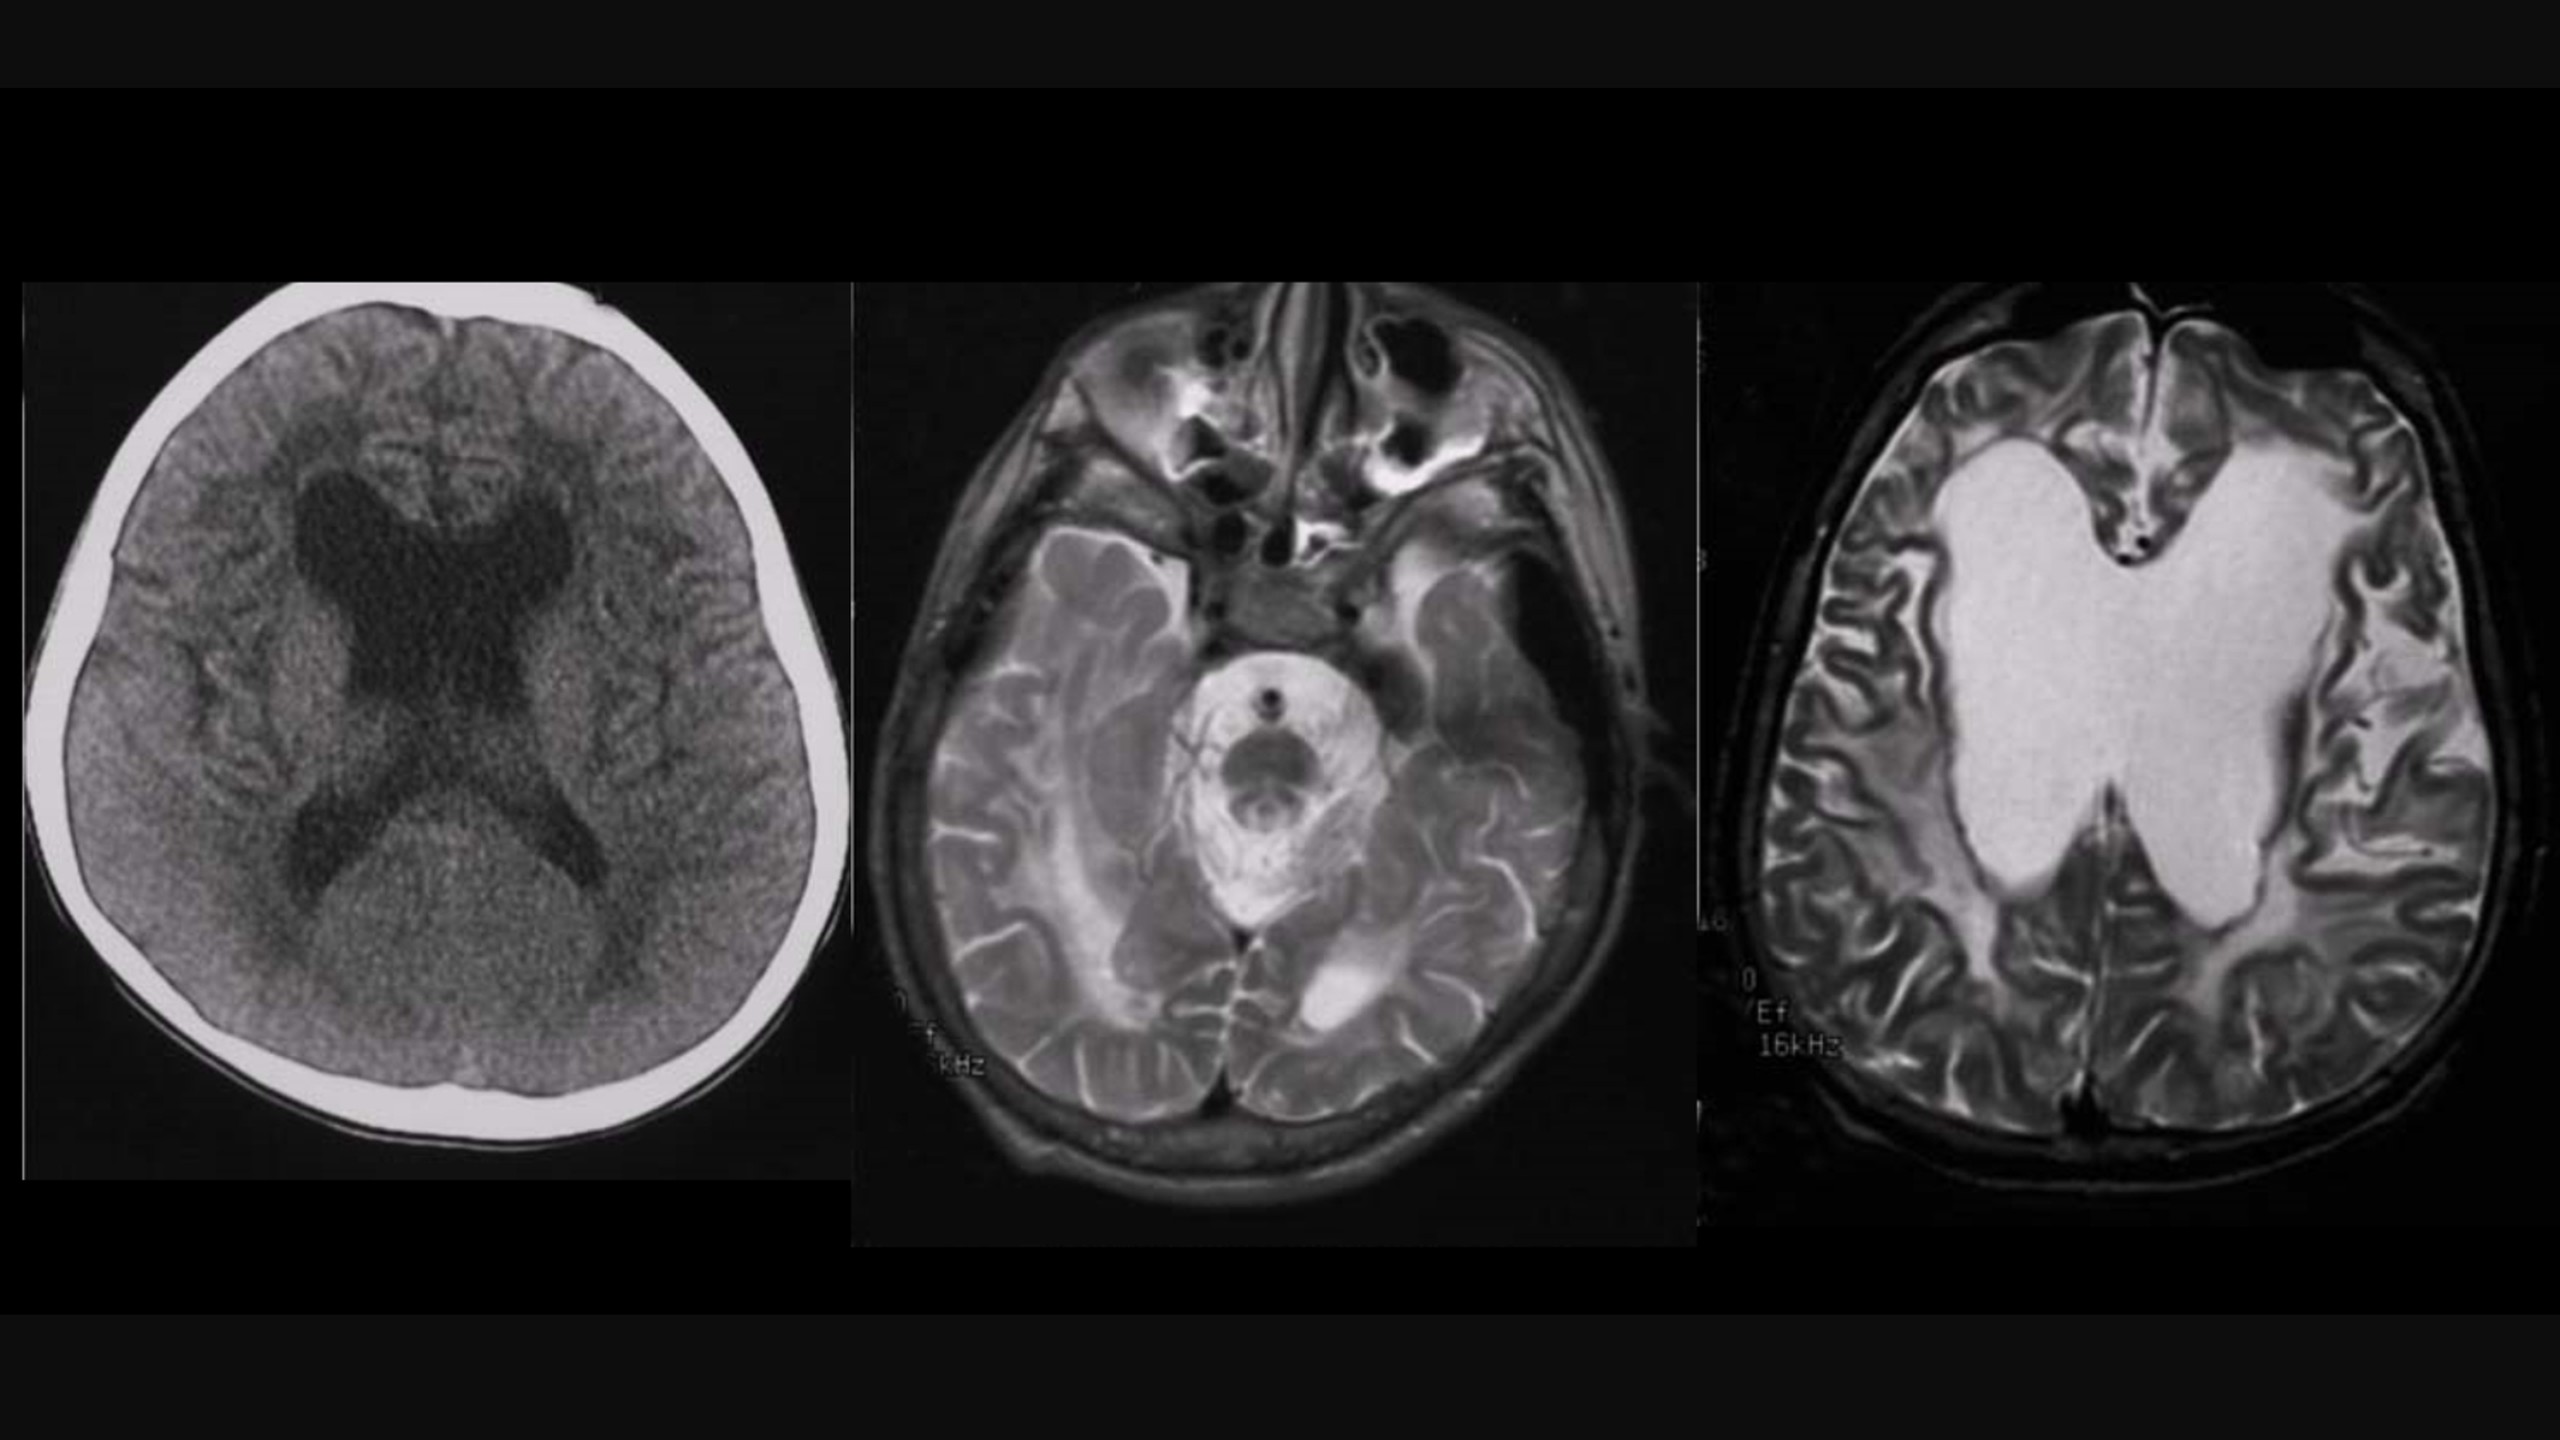

Các tổn thương chất trắng có thể được nhìn thấy bằng chụp cộng hưởng từ (MRI) với hình ảnh những điểm sáng trong não của bạn. Một số tổn thương chất trắng nếu nhỏ có thể không gây ra triệu chứng đáng chú ý. Nếu nhiều tổn thương chất trắng hơn sẽ biểu hiện nhiều triệu chứng hơn.

Để chẩn đoán bệnh thoái hóa chất trắng não, bác sĩ thường yêu cầu thực hiện chụp cộng hưởng từ (MRI) để quan sát rõ các tổn thương chất trắng trong não. Kết quả hình ảnh MRI cũng có thể giúp phát hiện các bất thường khác như khối u, xuất huyết não hoặc nhồi máu não. Ngoài ra, tùy vào từng trường hợp cụ thể mà bác sĩ có thể chỉ định thêm xét nghiệm như xét nghiệm lipid máu và đường huyết.